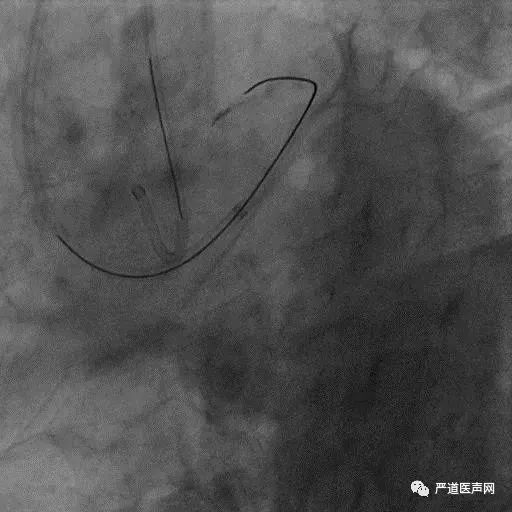

Case 2:Male,79 yrs old, Stable angina

March2015

5 hours later……

July2018

• No stump

• Lesion length > 20mm

• Severe tortuosity CC (Retro attempt failed)

• Diffuse lesion in target vessel

Step up: UB3 - GAIA Third - Conquest Pro

In side branch of LAD

KDL: GAIA Third

Step down: GAIA Third – UB3

Stingray balloon

Post blood drawn

Stick and swap to GAIA Third

Final Results

当逆向技术困难时,如解剖条件许可,应优选ADR